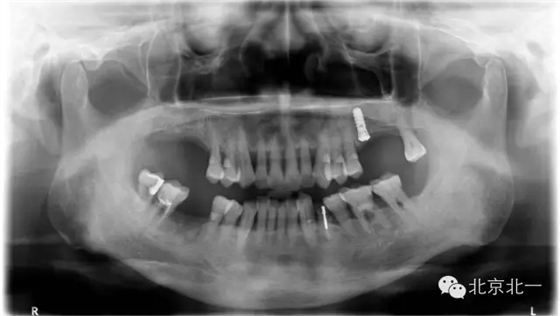

患者取模,最后無法脫模,和患者采用石膏取模異曲同工之妙!

分析:患者牙周病,前牙區(qū)間隙大, 倒凹明顯, 醫(yī)生沒有注意填倒凹導致無法脫模, 最后用手術刀破壞硅橡膠,鋼絲剪剪斷托盤后方取下托盤。非常慶幸不是鋼托盤呀!

預防措施:取模前切記要充填倒凹即可,特別是牙周病患者,至于什么材料充填可以很多選擇, 最簡單方便的就是蠟片。